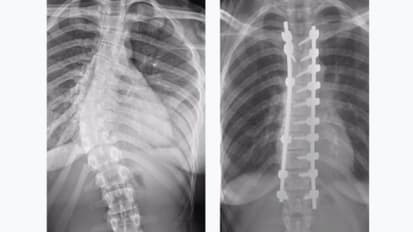

Scoliosis Correction Surgery Helps Patients Walk Tall

For patients with scoliosis, Charles Reitman, M.D., an orthopaedic surgeon at MUSC Health, performs corrective surgery to draw crooked spines back toward a more balanced and functional plane. But he will be the first to maintain that surgery ...